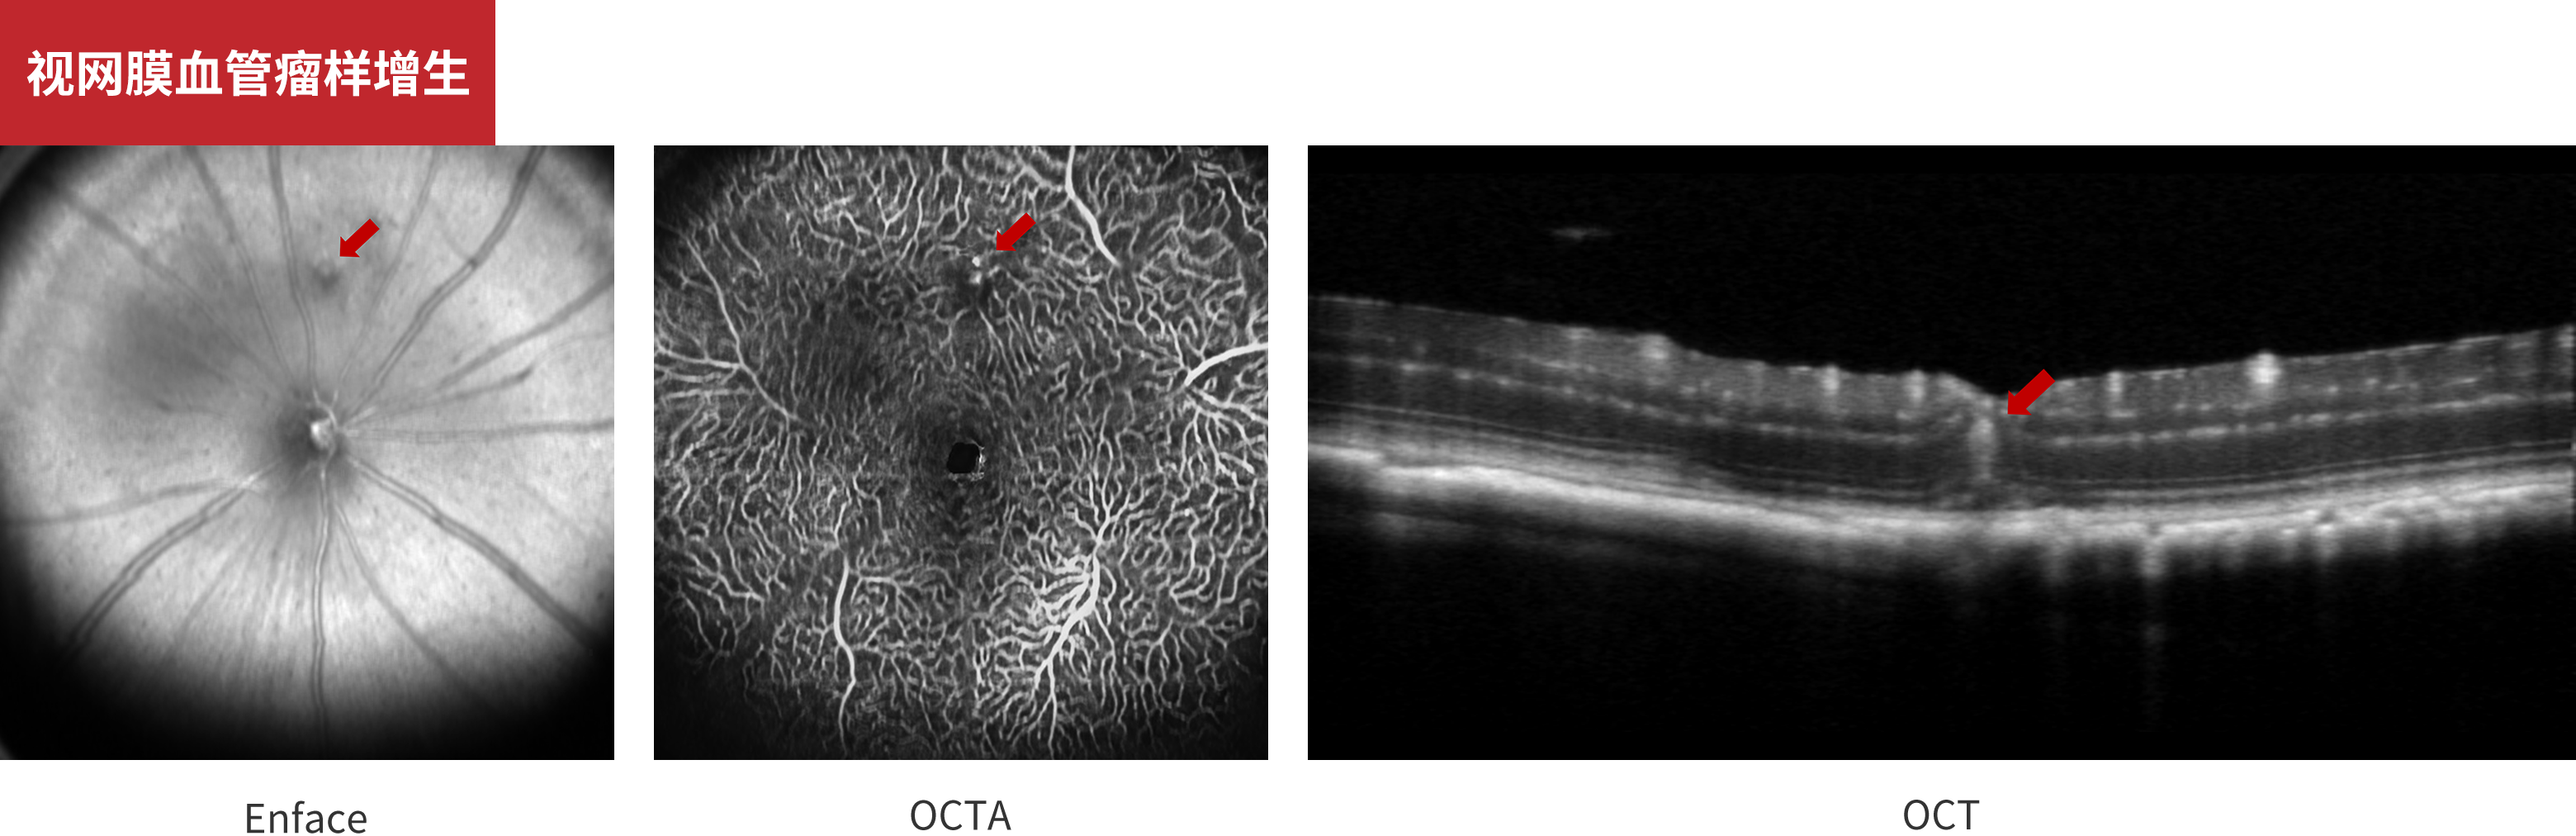

视网膜血管瘤样增生